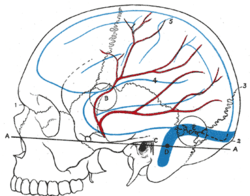

Relations of the brain and middle meningeal artery to the surface of the skull. (Nasion is at #1.) | |